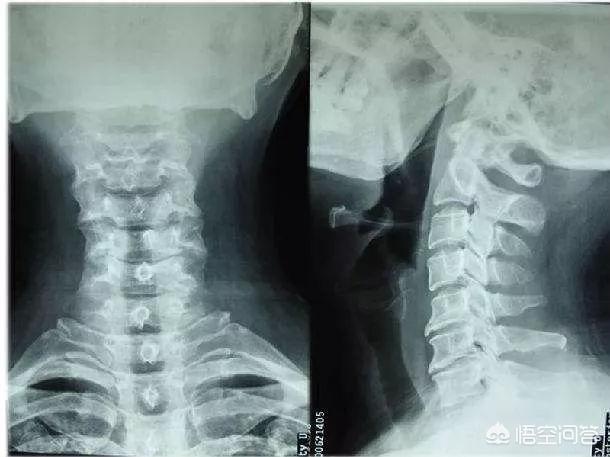

子供たちの学業へのプレッシャーは非常に高く、それは国際的にもよく知られている。もしこの子供が中学生か高校生であれば、脊椎に深刻な病変があると思われる。このような病巣が神経を圧迫し、刺激し続けることで、神経の障害につながる。患者が生物を発見するのが難しいのは、生物を持っていないからではなく、適切な場所で生物をチェックしていないからである。胸の痛みは心臓の問題ではないこともある、頭痛は頭の問題ではないこともある。

頚部や胸部のMRIや整形側面のフィルムで何か新しいことが見つかるかもしれないし、治療は決してやみくもに行わず、原因を治療する方がいい。